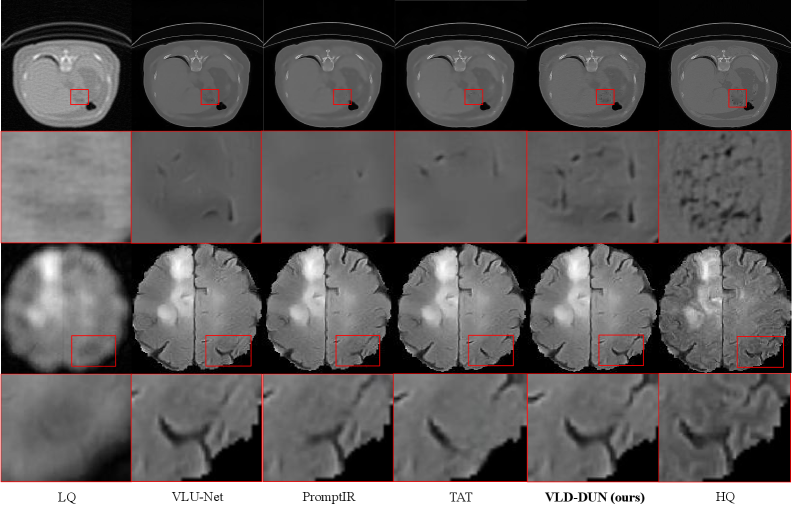

Figure 7: Visualization of Comparative Experiments. We provided visualizations of BrainTS2021 and COVID19-CT, and entire experiments are conducted on RTX pro 6000. Our VL-DUN is able to reconstruct more details and achieves state-of-the-art performance in reconstruction.

The quality result is shown in Table 1, demonstrating our VL-DUN achieves state-of-the art by improving 0.92dB in PSNR and 9.76% in Dice. The visual results are provided in Fig. 7 and Fig. 8, showing that our VL-DUN reconstructs in more details. This substantial improvement validates that our joint optimization strategy effectively leverages the synergy between tasks: the restoration branch provides clearer features for segmentation, while the segmentation branch imposes semantic constraints to prevent structural distortion during restoration. To provide a deeper understanding of this capability, we visualize the high-frequency components in Fig. 8. It is evident that our model, empowered by the Frequency-Aware Mamba mechanism, successfully decouples noise from texture. This allows VL-DUN to suppress artifacts while preserving high-frequency diagnostic details, addressing the spectral bias limitation common in conventional Mamba-based architectures.